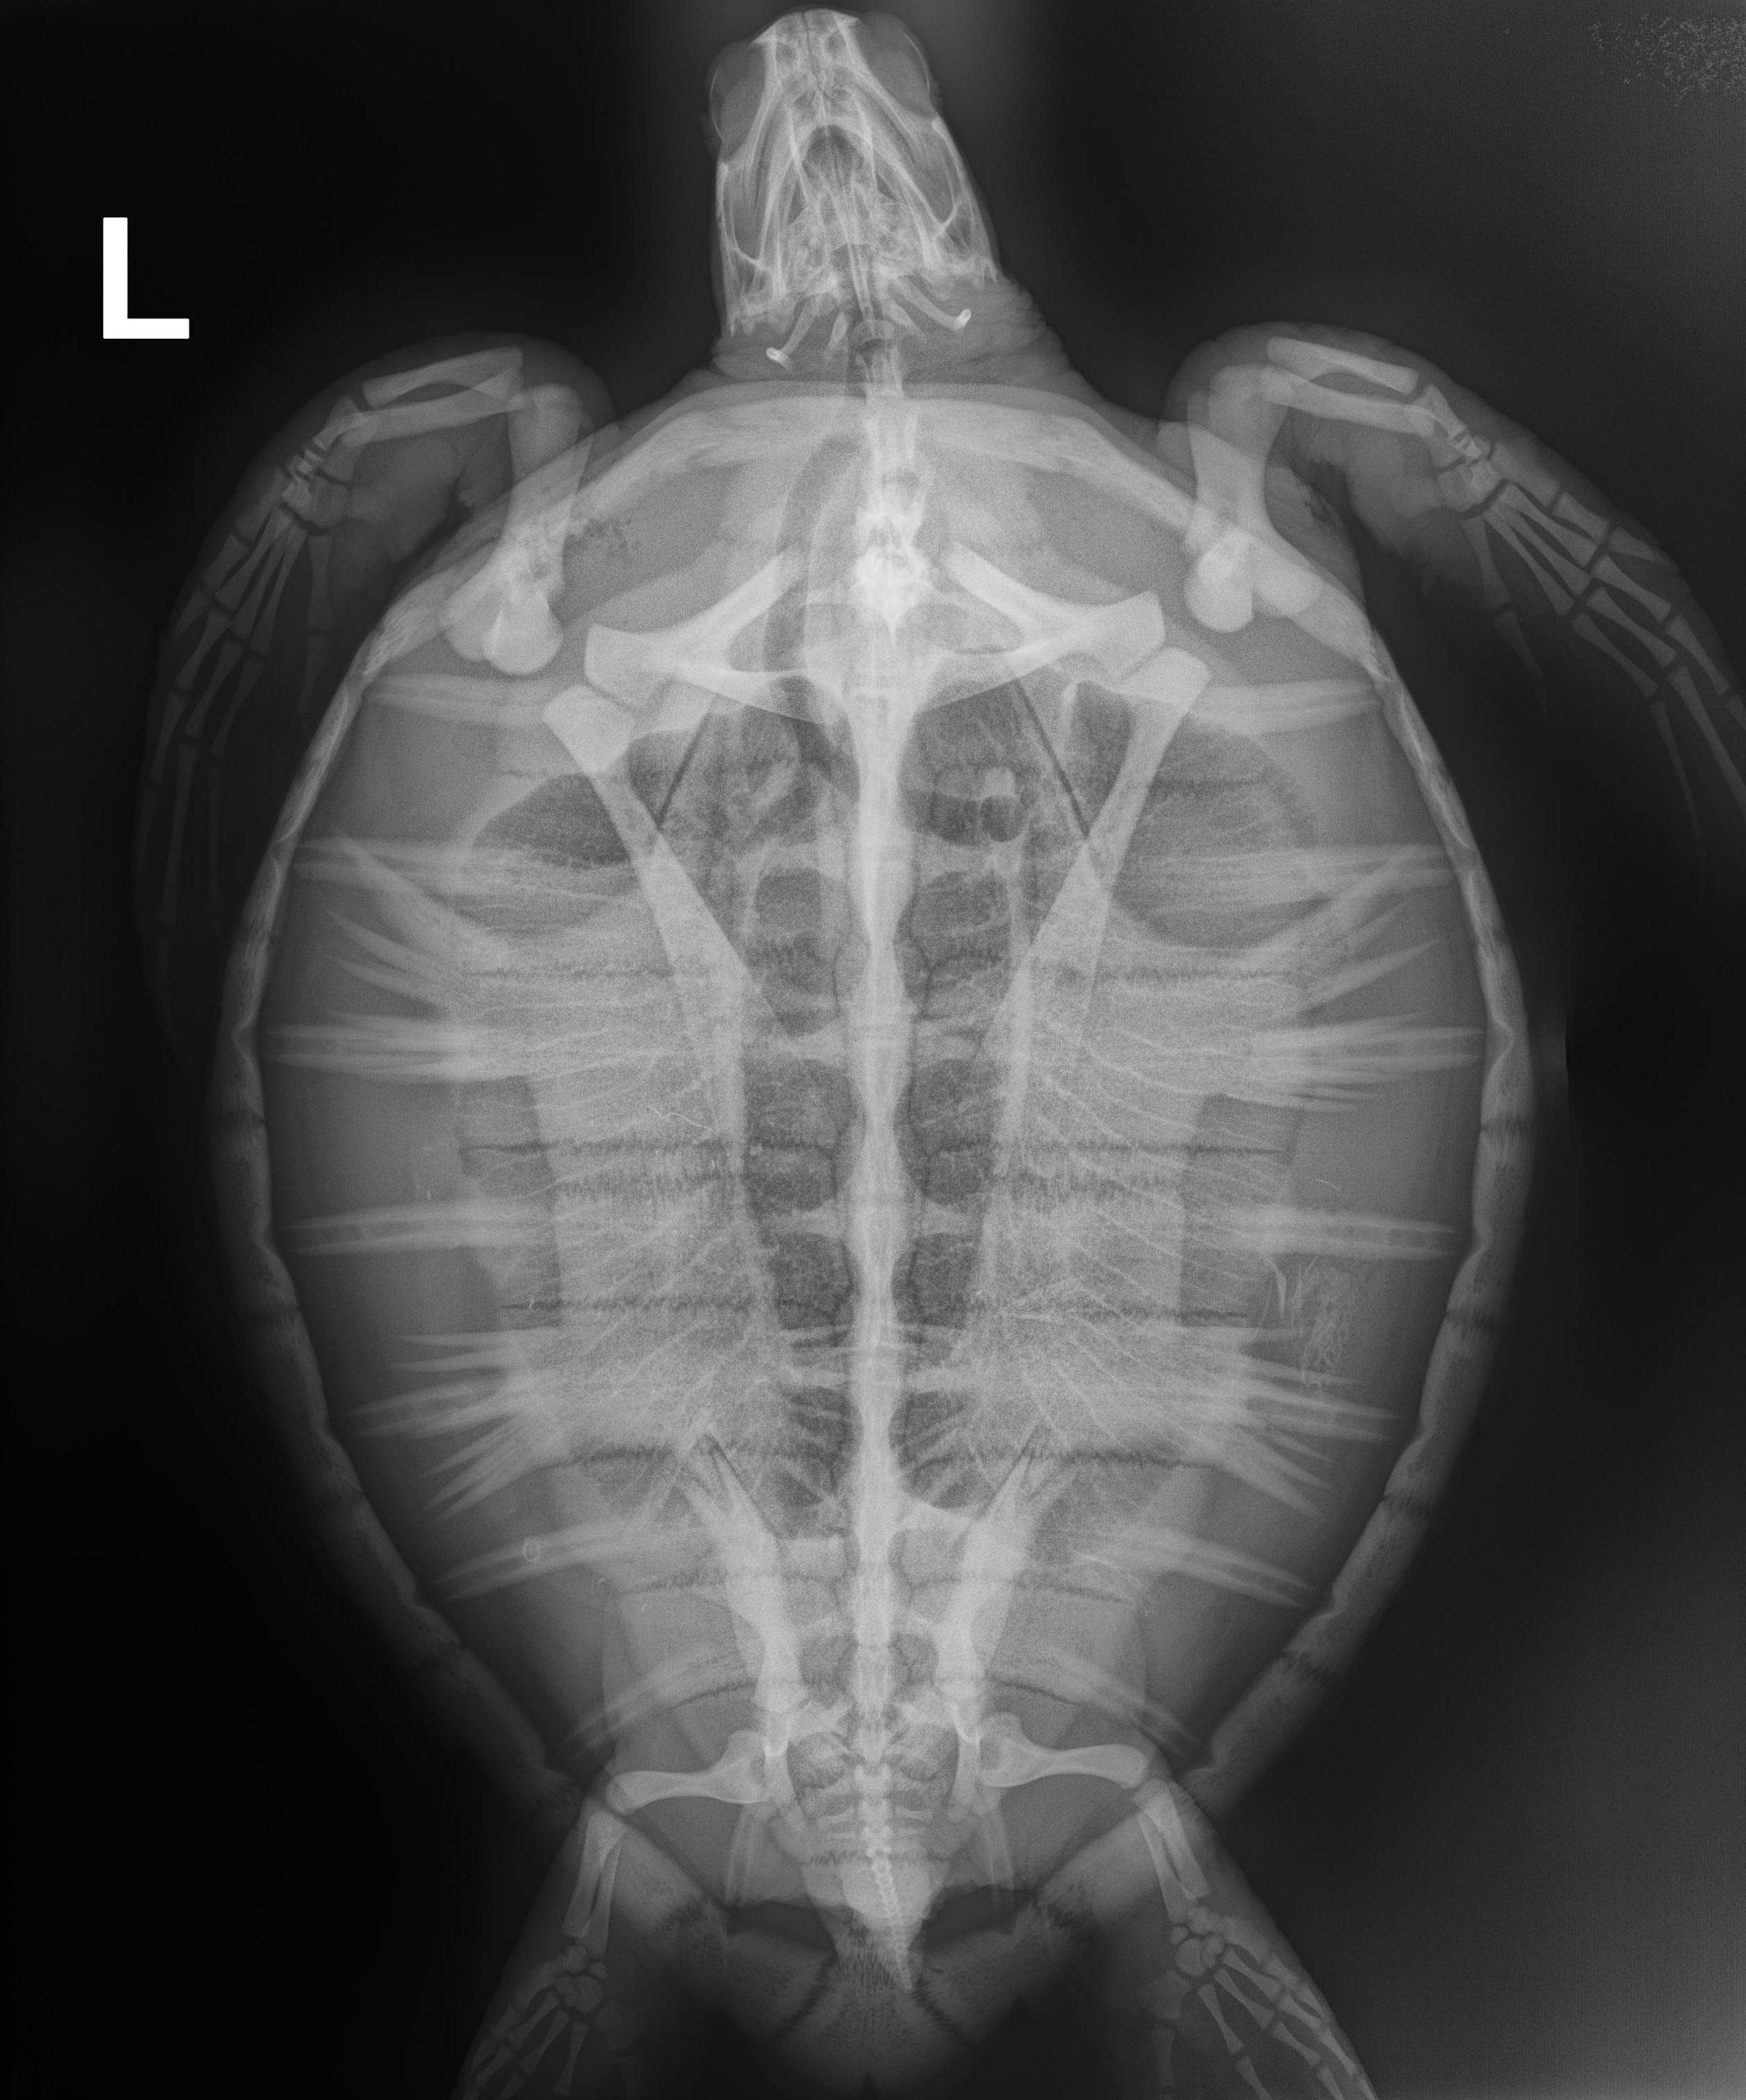

9.4 lbs. non -FP juvenile green

Hooked on left front flipper

In-house PCV = 30%, TP = 4.0 g/dl, glucose = 126. Started on Ceftaz, Vitamin B, and Normosol.